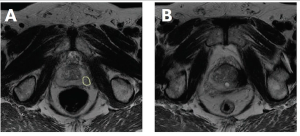

Advanced imaging and improvements in biopsy techniques usher in a new paradigm for screening and diagnosis.